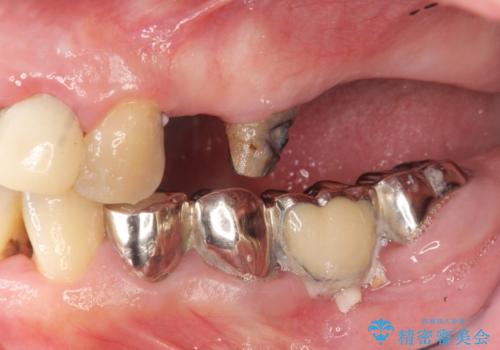

多発した虫歯による咬合崩壊 インプラントを用いた全顎治療

- 「これまで歯の治療をおざなりにしてしまい本当に後悔している。 時間と費用がかかってもいいので、しっかりと安心してかめるような状態にしてほしい。」、と全体的な治療を希望され来院されました。

歯の破折・再発した大きな虫歯・根尖病変・歯の欠損、これらの問題を根管治療・歯周外科・インプラント治療・セラミック補綴を行うことで一つづつ解決し安定した咬合状となるよう治療を進めます。